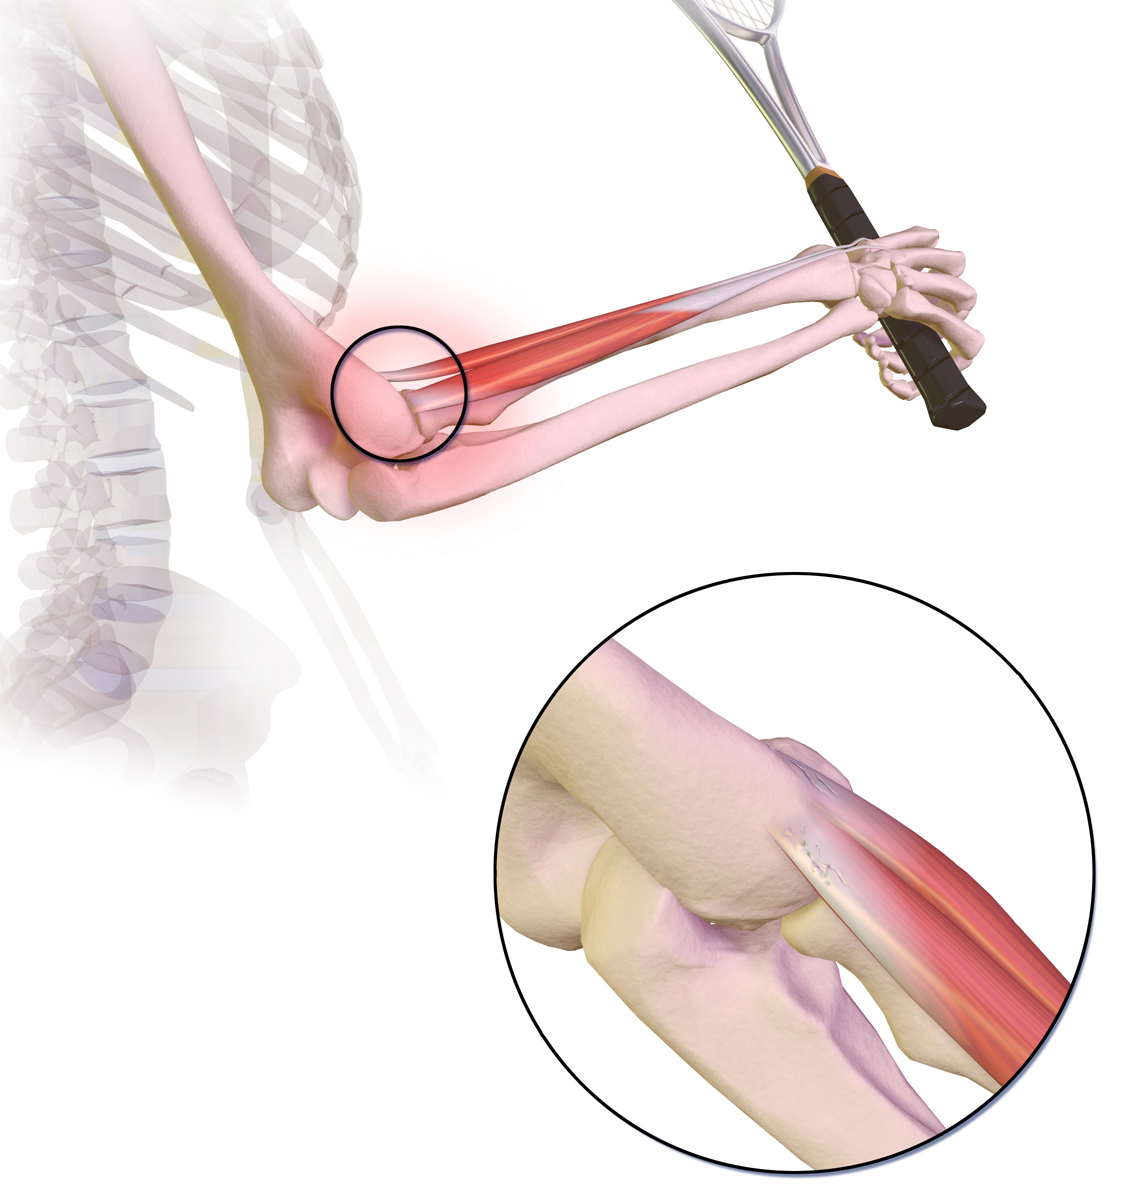

This picture shows where the pain is felt, on the outside of the elbow, in tennis elbow:

Tennis elbow

© BruceBlaus, CC BY-SA 4.0, via Wikimedia Commons

The following picture shows where the pain is felt, on the inside of the elbow, in golfer's elbow:

Golfer's elbow picture

© www.scientificanimations.com, CC BY-SA 4.0, via Wikimedia Commons